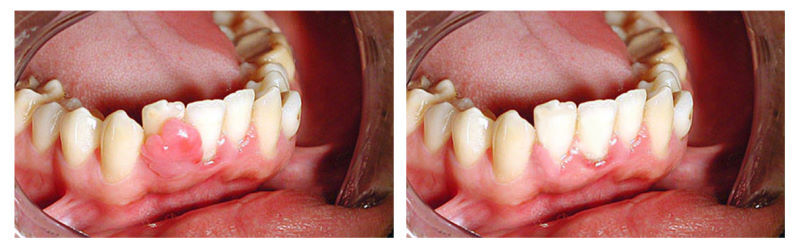

Удаление зуба с кистой: фото до и после